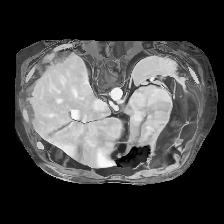

In clinical practice, well-aligned multi-modal images, such as Magnetic Resonance (MR) and Computed Tomography (CT), together can provide complementary information for image-guided therapies. Multi-modal image registration is essential for the accurate alignment of these multi-modal images. However, it remains a very challenging task due to complicated and unknown spatial correspondence between different modalities. In this paper, we propose a novel translation-based unsupervised deformable image registration approach to convert the multi-modal registration problem to a mono-modal one. Specifically, our approach incorporates a discriminator-free translation network to facilitate the training of the registration network and a patchwise contrastive loss to encourage the translation network to preserve object shapes. Furthermore, we propose to replace an adversarial loss, that is widely used in previous multi-modal image registration methods, with a pixel loss in order to integrate the output of translation into the target modality. This leads to an unsupervised method requiring no ground-truth deformation or pairs of aligned images for training. We evaluate four variants of our approach on the public Learn2Reg 2021 datasets \cite{hering2021learn2reg}. The experimental results demonstrate that the proposed architecture achieves state-of-the-art performance. Our code is available at https://github.com/heyblackC/DFMIR.